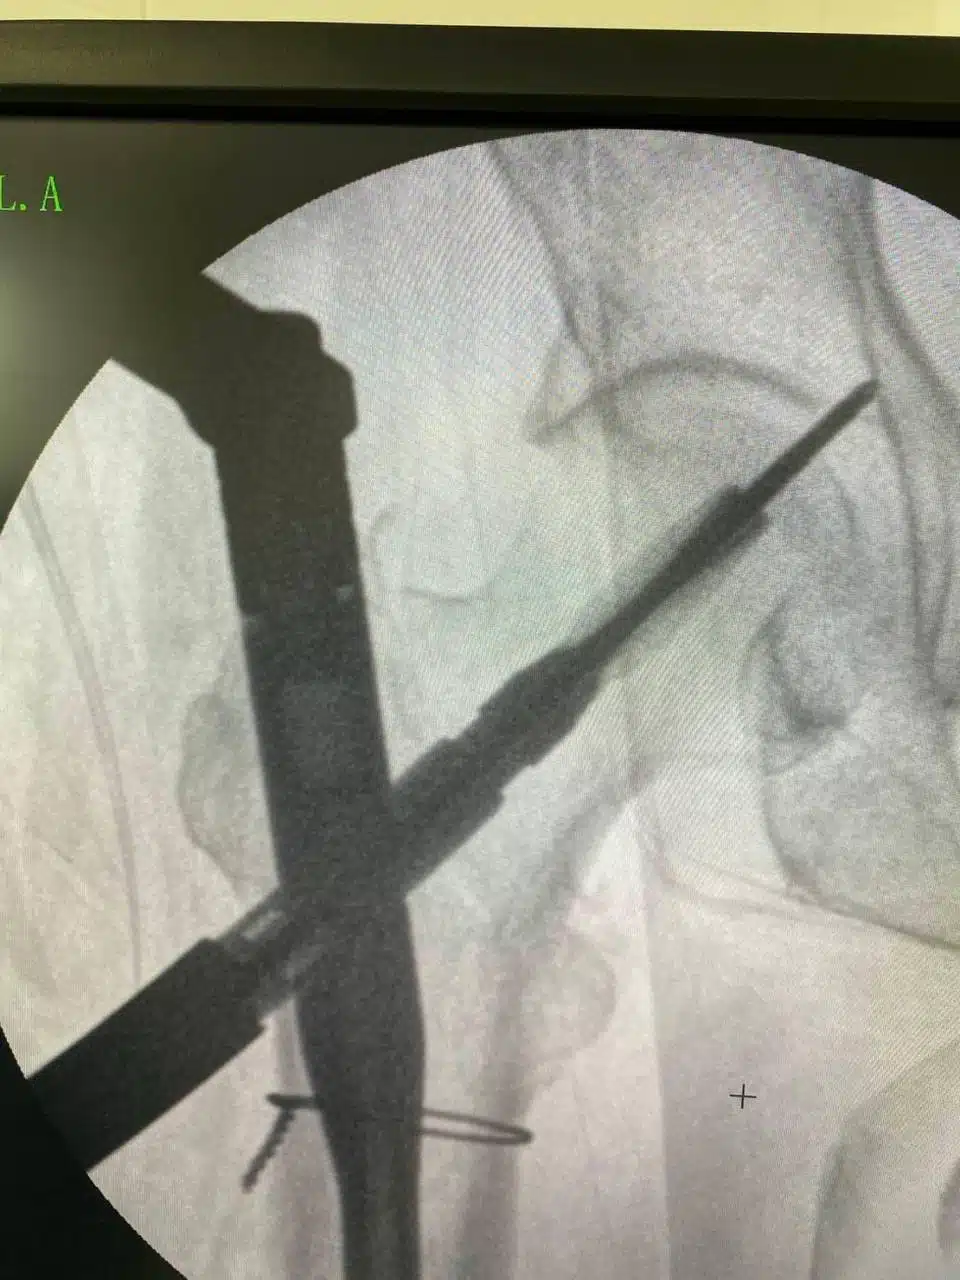

На сторінці КНП «Переяславська БЛІЛ» розповіли, що лікарі-ортопеди-травматологи продовжують проводити хірургічні втручання при переломах стегнових кісток за допомогою системи PFNA (long).

Так, цього тижня медичний колектив лікарні у складі лікарів Дмитра Мордовця, Юрія Зозулі, лікаря-анестезіолога Романа Максимця та медичної сестри Людмили Чепіги успішно прооперували пацієнтку 1947 року народження з діагнозом закритий перелом проксимального відділу лівої стегнової кістки. Операція пройшла без ускладнень, а пацієнтка почала процес реабілітації.